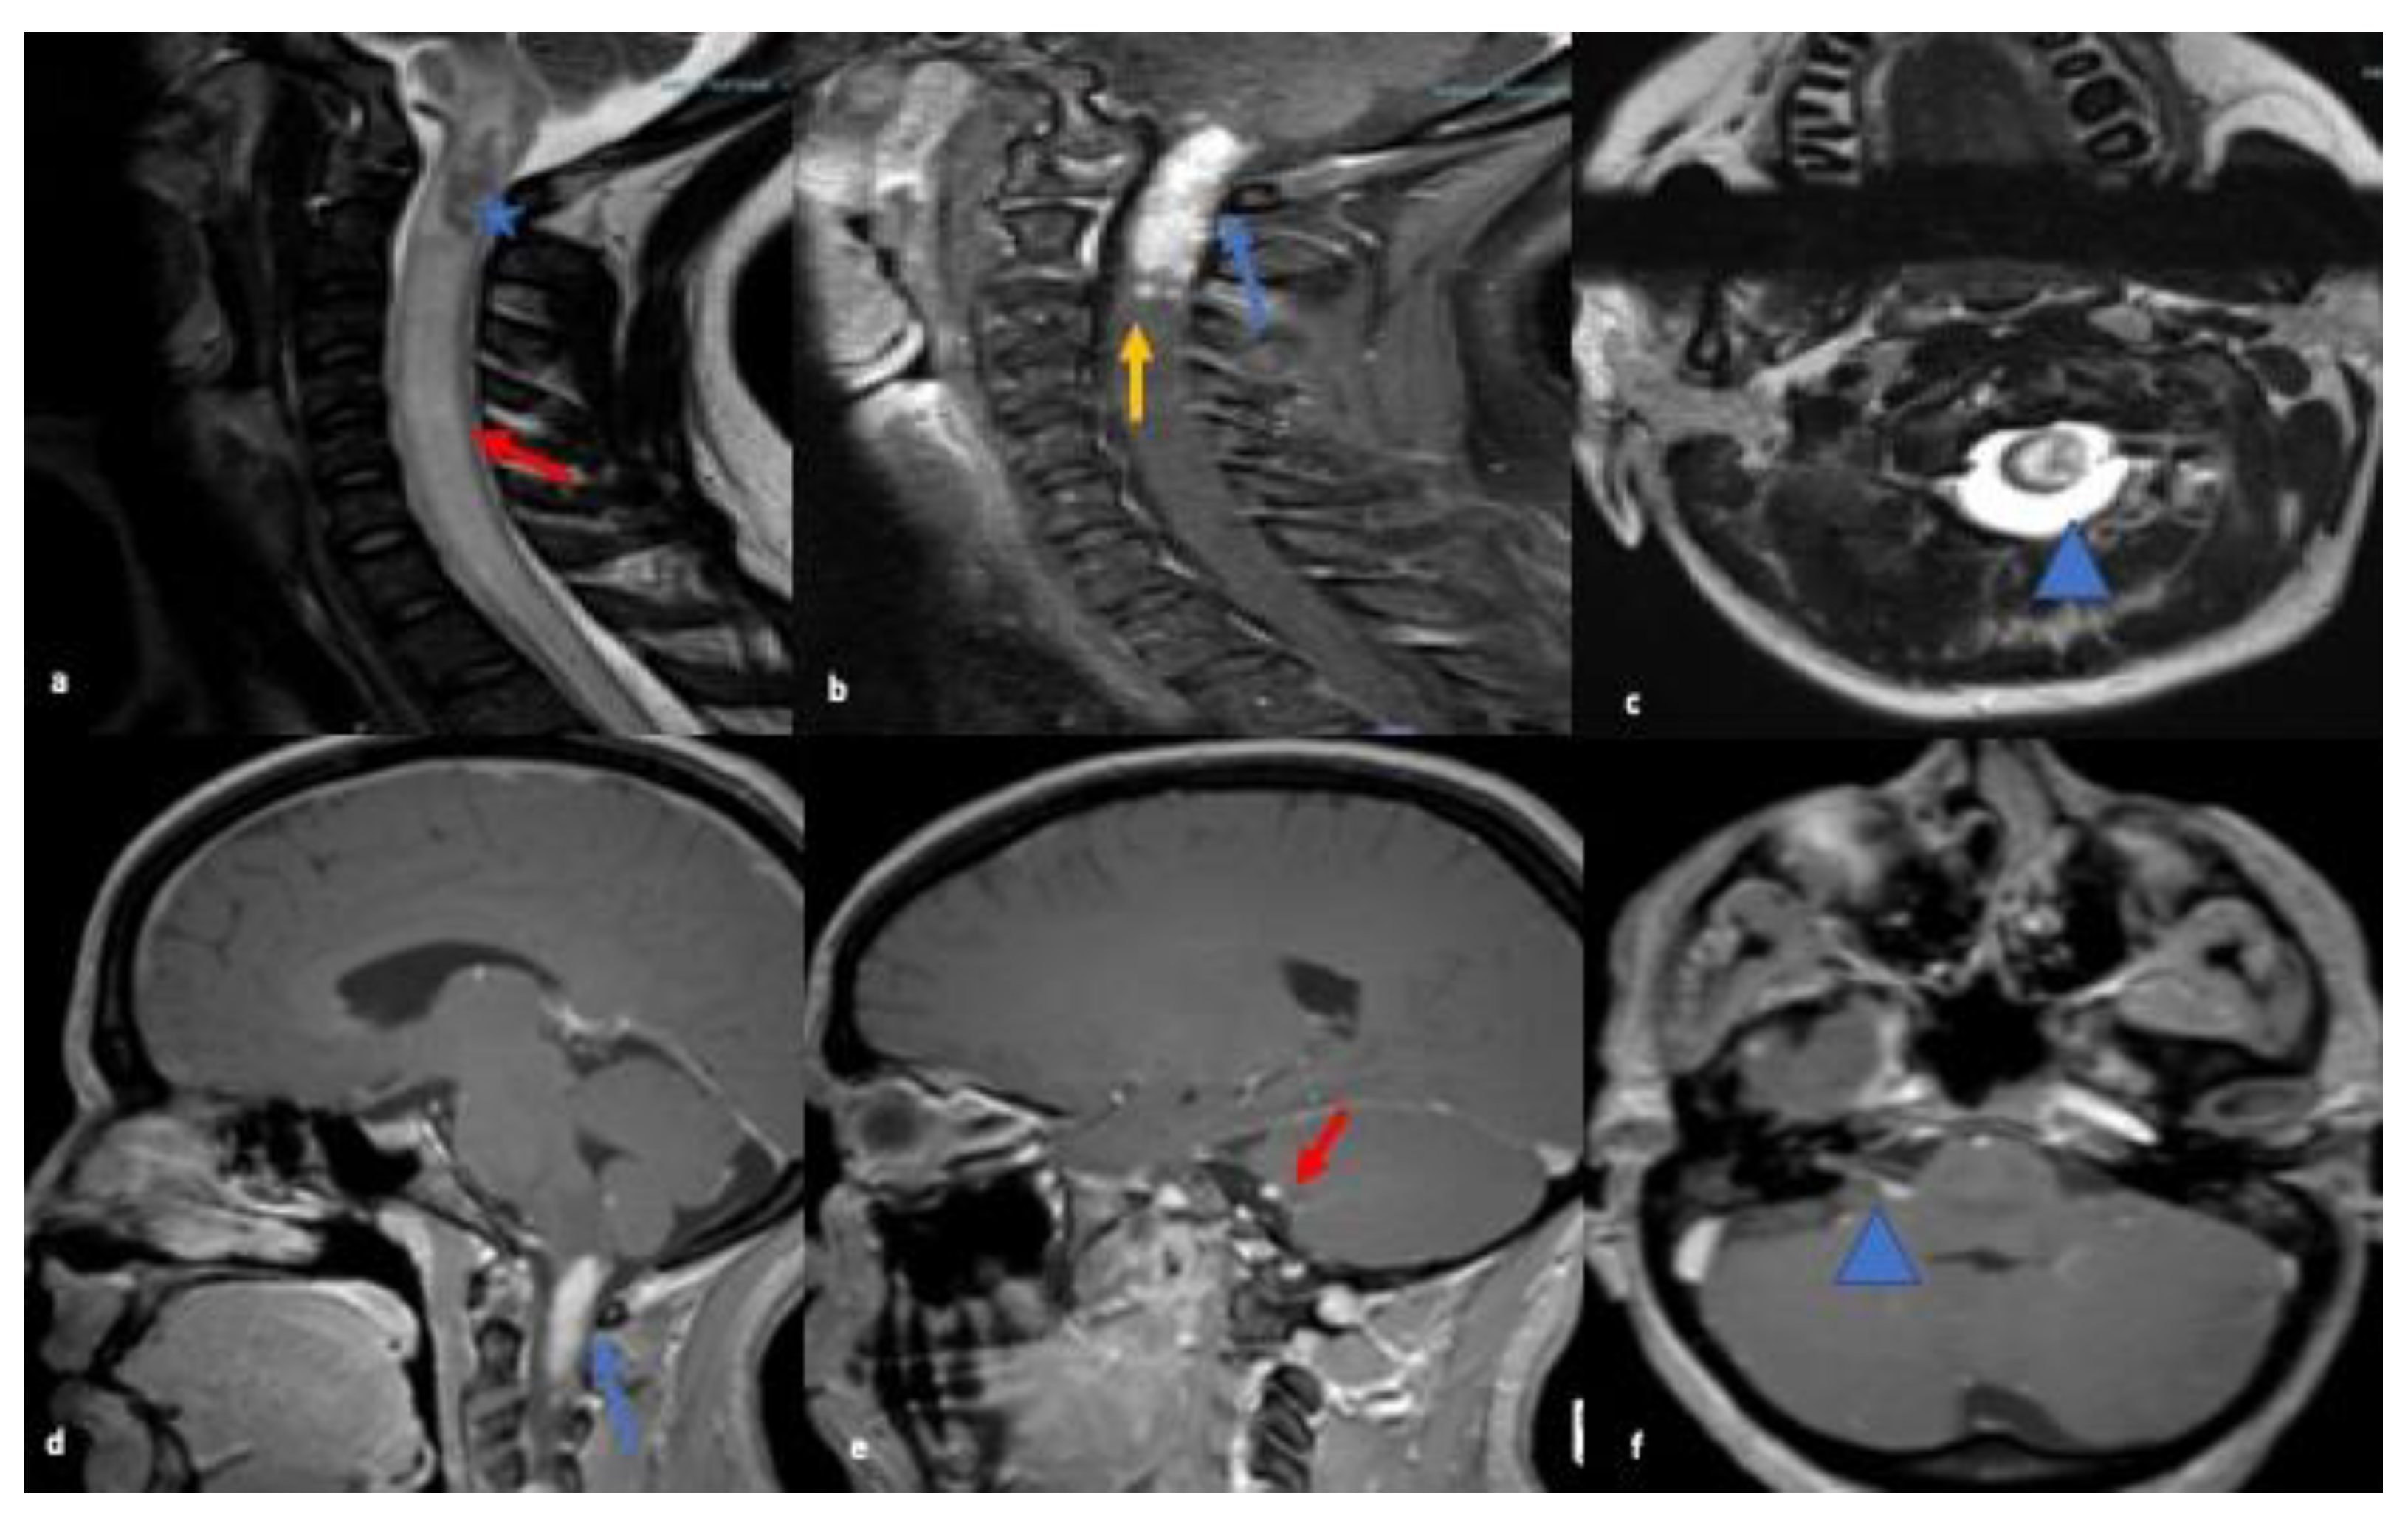

MRI brain showed abnormal enhancement within the right internal auditory canal with extension to the right cerebellopontine angle to the root of the VII and VIII cranial nerve complexes. MRI C-spine showed intramedullary enhancing lesions extending throughout the cervical spinal cord spanning C1 and C2. Multiple subtle foci of enhancement were also noted at C3 and within the lateral aspect of the medulla (refer to Figure 1). CT chest/abdomen/pelvis were without evidence of malignancy or systemic sarcoid.

Figure 1.

MRI sagittal T2 images (a) of the cervical spine reveal ill-defined long segment signal alteration with prominent cord expansion (red arrow) and ill-defined heterogenous lesion in cervicomedullary junction of the cord (blue asterisk); and (b) T1 post contrast image shows cord enhancement (blue arrow) and multiple separated subtle foci of enhancement were noted at C3 (yellow arrow). Axial T2-weighted (c) reveals corresponding hyperintense cord signal (blue arrowhead). MRI Brain sagittal and axial T1 post contrast images highlights homogenous enhancement at cervicomedullary junction (blue arrow; (d)), and enhancement along CN VII and VIII nerve complex (red arrow; (e)) & (blue arrowhead; (f)).

NS can affect the neurological system in various ways. One of these is cranial nerve involvement. Any of the cranial nerves can be involved in NS [11] but the most frequently reported is cranial nerve VII [1]. The first case in our series presented with lower motor neuron VII nerve palsy and VIII nerve involvement leading to a misdiagnosis of Bell’s palsy and ear infection. Multiple cranial nerve involvement, lesion within the brainstem and intramedullary lesions within the upper cervical spinal cord were seen on MRI were present in this case of NS. Despite treatment with steroids, the patient did not initially show improvement, complicating the case even further. The second case, initially diagnosed as orbital cellulitis, also demonstrated multiple cranial nerve involvement with ophthalmoplegia secondary to infiltration of the extraocular muscles due to granulomatous masses. The patient experienced loss of vision in the left eye due to surrounding inflammatory changes and mass effect. A subsequent biopsy confirmed the diagnosis of orbital sarcoidosis. Hence, cranial nerve involvement with other CNS lesions should raise suspicion for NS and treatment with steroids may not show a significant response initially.

Spinal cord predominant NS may involve leptomeningeal, pachymeningeal, and intramedullary regions, mimicking other myelopathies presenting with sensory, motor, and autonomic dysfunction [17,18,19]. Cervical and thoracic segment involvement is more commonly reported than lumbosacral involvement, similar to our case [19,20,21]. Junger et al. organized MRI manifestations ranging from Stage 1, indicating early inflammation to Stage 4, indicating progressive spinal cord atrophy [20].

Our first case presented with diffuse abnormal T2 signal throughout the cervical cord and intramedullary cervical cord enhancement with no cord atrophy consistent with stage 1 disease and involved more than three vertebral segments. In the past, authors have recommended using the length of spinal cord signal abnormality to aid in etiology of the lesions [14,17,18,19,20]. NS most commonly presents as multisegmental disease spanning multiple levels in the cord, uncommon in multiple sclerosis where plaques are usually shorter than two vertebral body lengths. However, longitudinally extensive spinal cord lesions (>3 vertebral segments on MRI examination) with acute myelitis are a characteristic feature of neuromyelitis optica spectrum disorders (NMOSD), which closely mimics NS, often leading to misdiagnosis [22,23]. Meningeal enhancement or persistent enhancement (more than a few weeks) of parenchymal lesions are much more suggestive of sarcoidosis than NMO [24]. Also, testing for the NMO/AQ-4 antibody is helpful in this setting, and was negative in our patient.